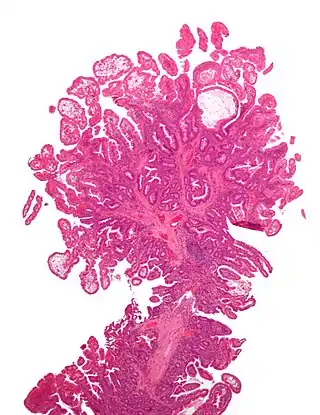

El síndrome de Peutz-Jeghers es una enfermedad autosómica dominante, se caracteriza por la producción y la presencia de pigmentaciones epidérmicas, además de la presencia de hamartomas gastrointestinales; este hecho fue confirmado en 1987 por Giardello, el cual, reporto 31 casos de síndrome de Peutz-Jeghers, con daño gastrointestinal asociado a hamartomas.[1]

Generalmente la presencia de estos síntomas como los hamartomas no se considera perjudicial o maligna, pero, en el síndrome de Peutz-Jeghers varios autores han reportado casos con excesivo daño gastrointestinal. La presencia de las pigmentaciones suele ocurrir por el desplazamiento epitelial debajo de la capa muscular.[1]

No existe una presentación típica del síndrome de Peutz-Jeghers,[3] sin embargo, en algunos pacientes suele predominar las hiper pigmentaciones muco-cutáneas acompañados de pólipos intestinales que a su vez desencadenan cólicos gastro intestinales de moderada o severa intensidad, los mismos causan rectorragia ya sea esta oscura (melenas) o clara (hematoquecia).[5]

Los pólipos intestinales son hamartomas que tienen solo una pequeña probabilidad de transformarse en malignos. Sin embargo, el síndrome de Peutz- Jeghers predispone a quienes lo padecen a un aumento del riesgo de aparición de tumores intestinales y extraintestinales malignos.[8] Así a nivel general los enfermos con el síndrome de Peutz- Jeghers tienen un mayor riesgo de padecer cáncer pancreático-biliar. Situación que se acrecienta con la edad teniendo: un riesgo del 1-2 % a los 20 años, >30 % a los 50 años y más del 80 % a una edad de 70 años.[8] En este sentido muchos niños de tan solo 13 años de edad fueron diagnosticados con adenocarcinoma.[9] Personas de aproximadamente 30 años tienen un 5 % de riesgo de padecer cáncer a esta edad y siendo este porcentaje acumulativo ya que este aumenta a un 85 % a los 70 años.[10] En cuanto que el sexo más afectado por el riesgo cancerígeno es el femenino sobre todo para las variantes gastrointestinales, pancreáticas y ginecológicas cervicales, adenoma de cuello uterino y cáncer de mama con una frecuencia de 8 % a los 40 años y un 31 % a los 60 años.[3]